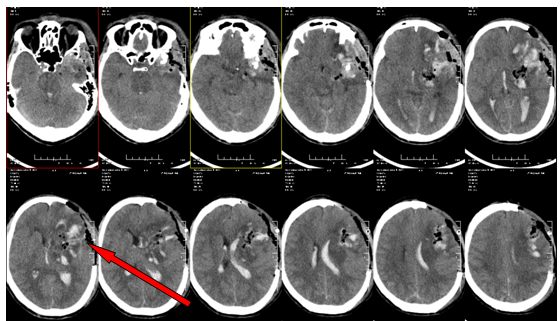

▲术后检查